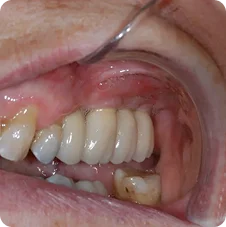

Final - Crown Placements

Crown Placements

Final